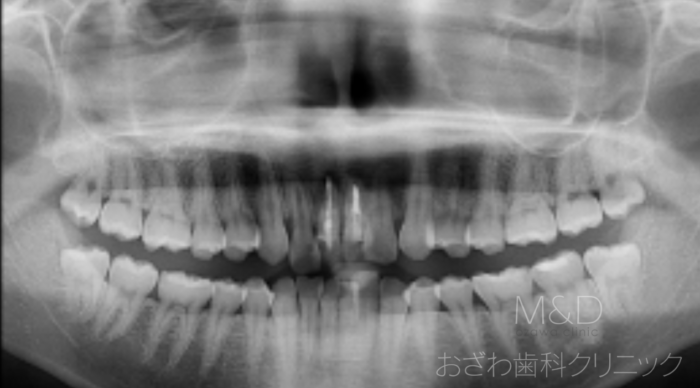

術前

主訴:歯根破折(前歯の欠損)

治療内容

上顎前歯の抜歯、骨造成手術(GBR)